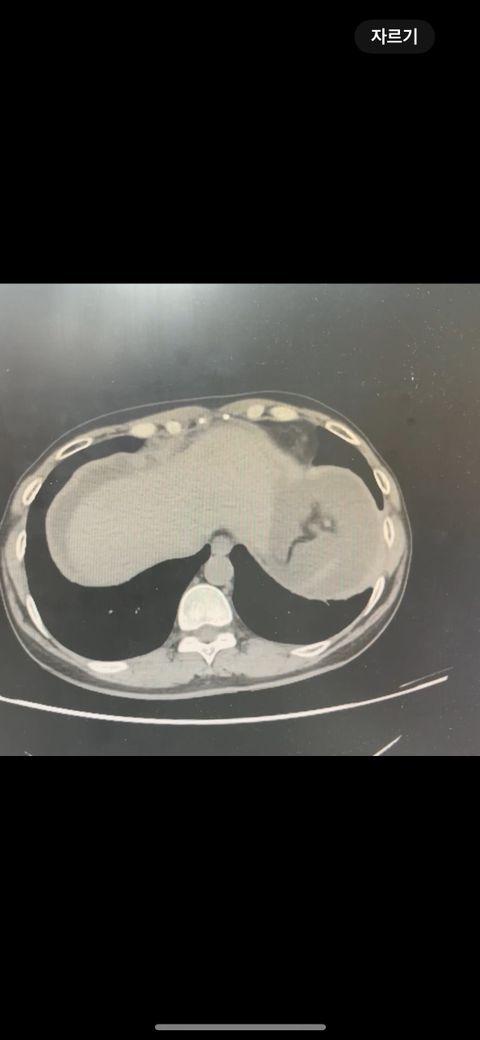

복부 ct 영상 판독부탁드립니다.!

결과는 3일 후 볼 예정인데 우선 영상만 받은 상태이고 너무 궁금한데 영상가지고 판독을 못해서요,,

이 사진가지고 확인할 수 있을까요 ?